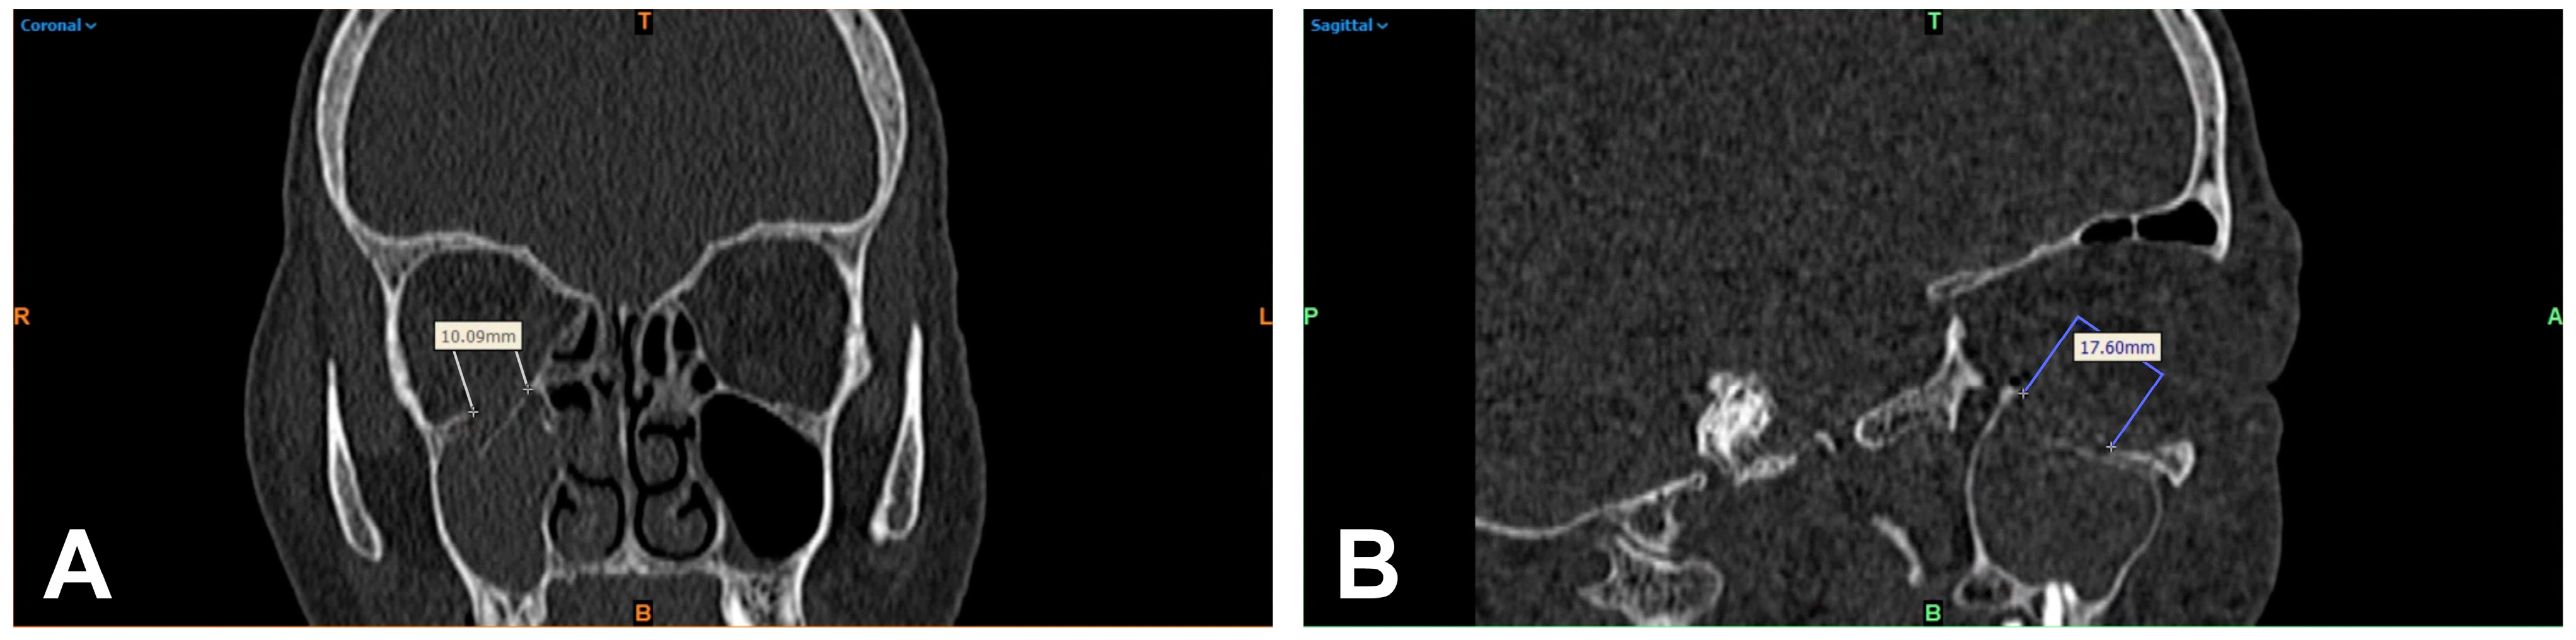

2.2. 2D-Based Measurement of Orbital Floor Fractures

2.3. 3D-Based Measurements of Orbital Floor Fractures